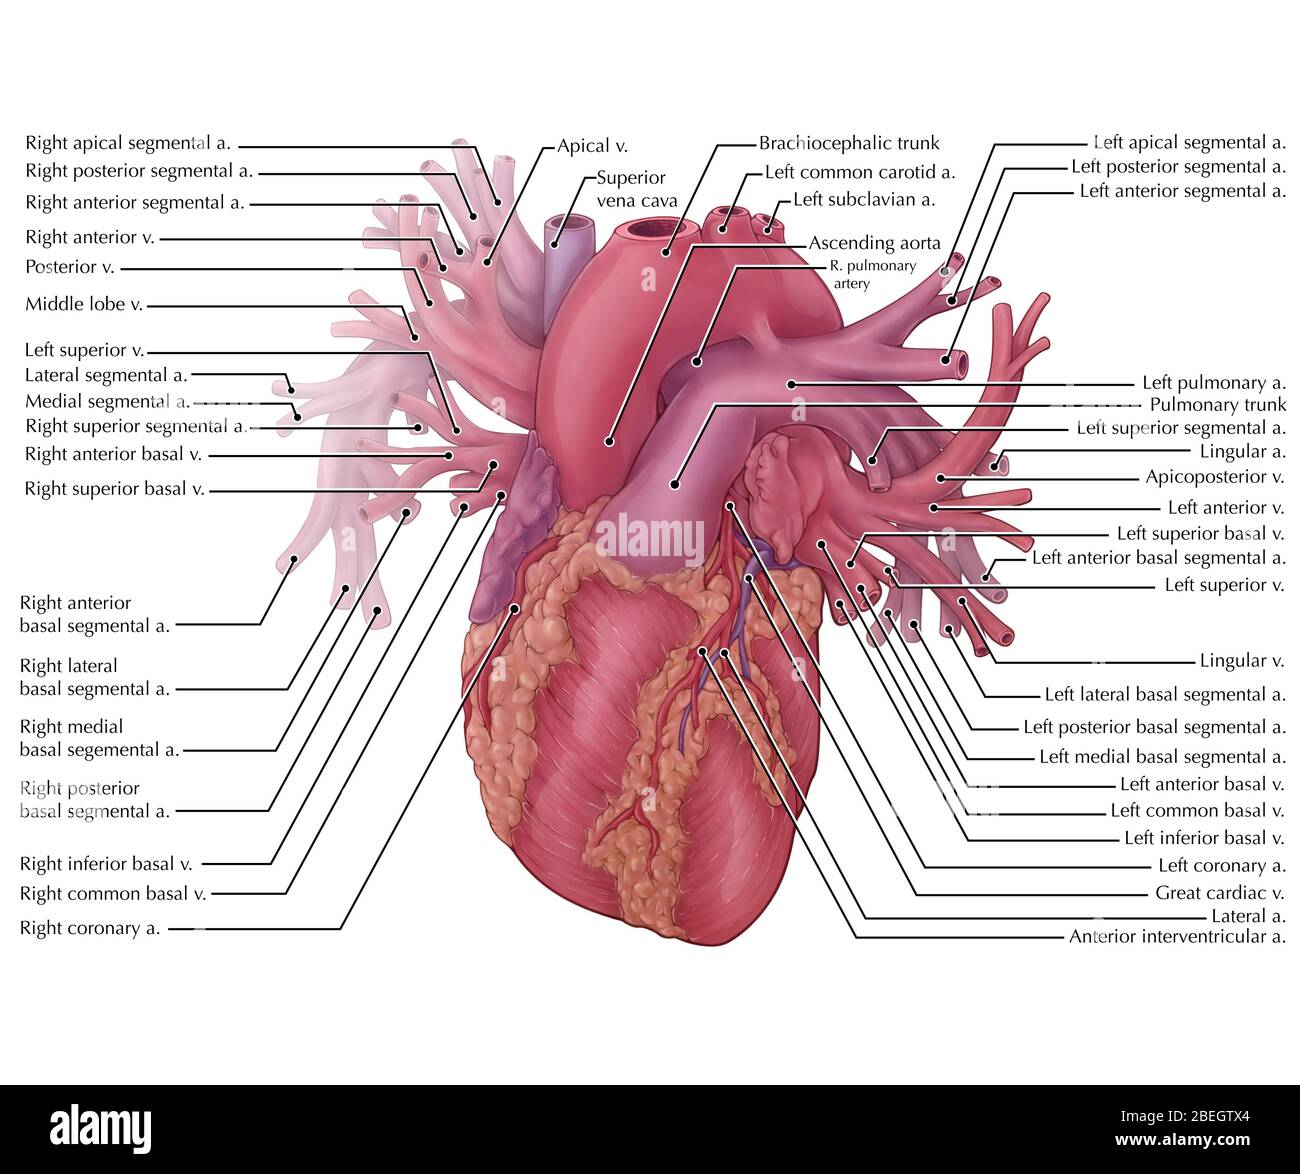

Vessels of the Heart Stock Photohttps://www.alamy.com/image-license-details/?v=1https://www.alamy.com/vessels-of-the-heart-image353183324.html

Vessels of the Heart Stock Photohttps://www.alamy.com/image-license-details/?v=1https://www.alamy.com/vessels-of-the-heart-image353183324.htmlRM2BEGTX4–Vessels of the Heart